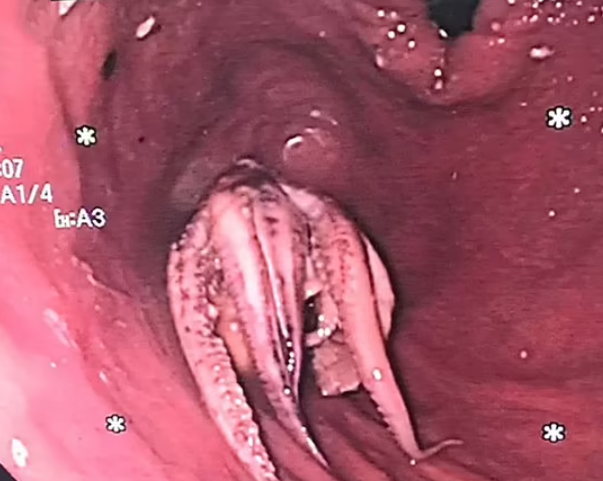

În cele din urmă, medicii au folosit forcepsul pentru a extrage capul caracatiței. Pacientul și-a revenit rapid după procedură și a fost externat două zile mai târziu.

Descoperirea șocantă făcută de medici în esofagul unui pacient / Sursa foto: Clinical Gastroenterology and Hepatology